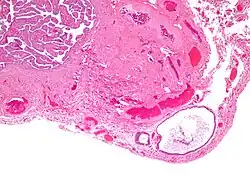

High magnification micrograph of a Brenner tumor showing the characteristic coffee bean nuclei which are also seen in Walthard cell rests. H&E stain.

They appear as white/yellow cysts or nodules that can reach a size of 2 millimeters. They typically have elliptical nuclei with a long groove (along the major axis) – so-called "coffee bean" nuclei.

- Cyst (may also be solid nest) of transitional type epithelium.

- Eosinophilic luminal secretions.

- Uniform nuclei with irregular borders and nuclear grooves (insert image).